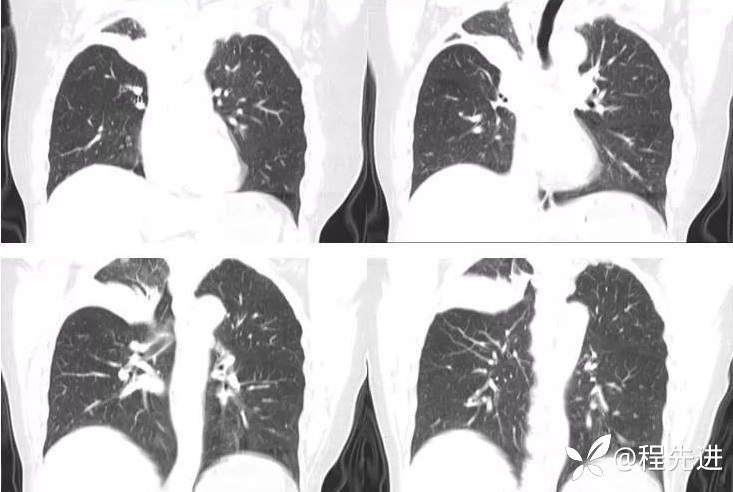

外院胸部CT平扫:右上肺病变,其内见散在高密度影

本院胸部CT增强: